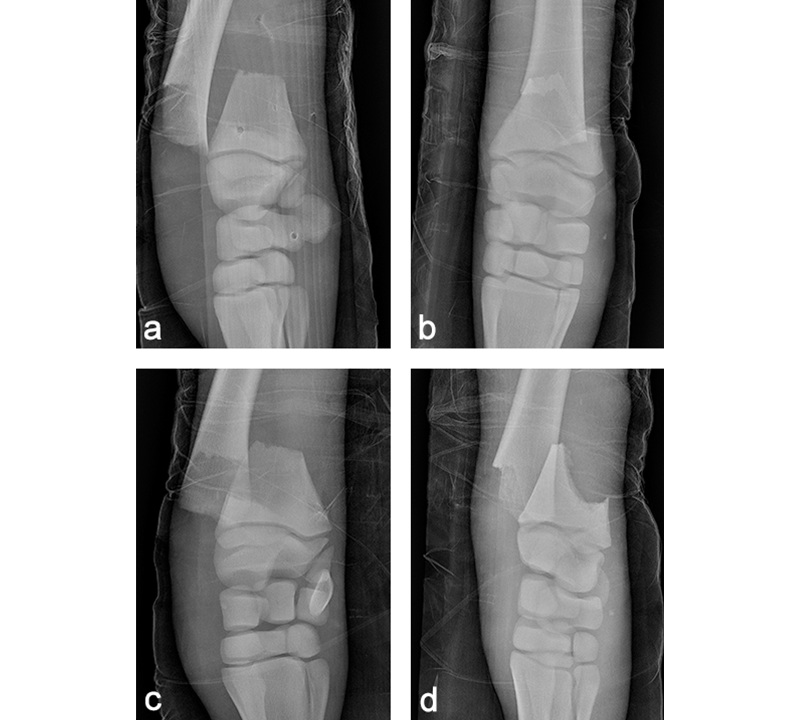

A 68 kg Warmblood foal was presented for evaluation and treatment of a complete open fracture of the left distal radius sustained during parturition 4 hours earlier. The fracture had occurred when the mare laid down against the wall of the stables while the foal was partially through the birth canal. The foal had been recumbent since birth. The limb had been partially stabilized with a full limb bandage and lateral splint prior to admission. The radiographs confirmed the presence of a complete slightly oblique (proximomedial to distolateral) open fracture, just proximal of the distal radial physis (Fig 10). Extensive maceration of the medial soft tissues just proximal of the carpus was noted, with a 0.5 cm full thickness skin laceration. The foal was stabilized and was taken to surgery a few hours following admission.